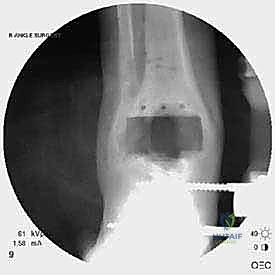

مراجعة مفصل الكاحل الصناعي هي إجراء جراحي ضروري لمعالجة المشاكل التي قد تنشأ بعد الجراحة الأولية، مثل كسور الكعبين أو عدم استقرار المفصل. يتضمن العلاج التشخيص الدقيق عبر الأشعة السينية والتصوير المقطعي، يليه التدخل الجراحي لتثبيت الكسور واستعادة وظيفة الكاحل، مع التركيز على التعافي المبكر.

تُعد جراحة مراجعة مفصل الكاحل الصناعي (Revision Total Ankle Replacement) من الإجراءات الجراحية المتقدمة والبالغة الدقة في عالم جراحة العظام الحديثة. لا تقتصر هذه الجراحة على مجرد استبدال مفصل تالف بآخر جديد، بل هي عملية إنقاذ معقدة للغاية تهدف إلى معالجة المشاكل الميكانيكية والبيولوجية التي تنشأ بعد الجراحة الأولية. من أبرز هذه المشاكل: الفشل الميكانيكي للمفصل، تحلل العظام (Osteolysis)، أو حدوث كسور معقدة في الكعبين (Malleolar Fractures) المحيطة بالمفصل الصناعي. يتطلب هذا الإجراء تقييماً سريرياً وشعاعياً دقيقاً يشمل التصوير المقطعي ثلاثي الأبعاد والأشعة السينية، يليه تدخل جراحي دقيق لاستعادة التوازن الحيوي والميكانيكي للكاحل والحفاظ على الطرف من البتر أو الدمج.

الخطوة الخامسة: تركيب المفصل الجديد أو الدمج

يتم إدخال المفصل الجديد المخصص للمراجعة، والذي يحتوي غالباً على سيقان (Stems) تدخل عميقاً في عظمة الساق وعظمة الكاحل لضمان الثبات الميكانيكي. في حال وجود كسور في الكعب، يتم تثبيتها في هذه المرحلة.